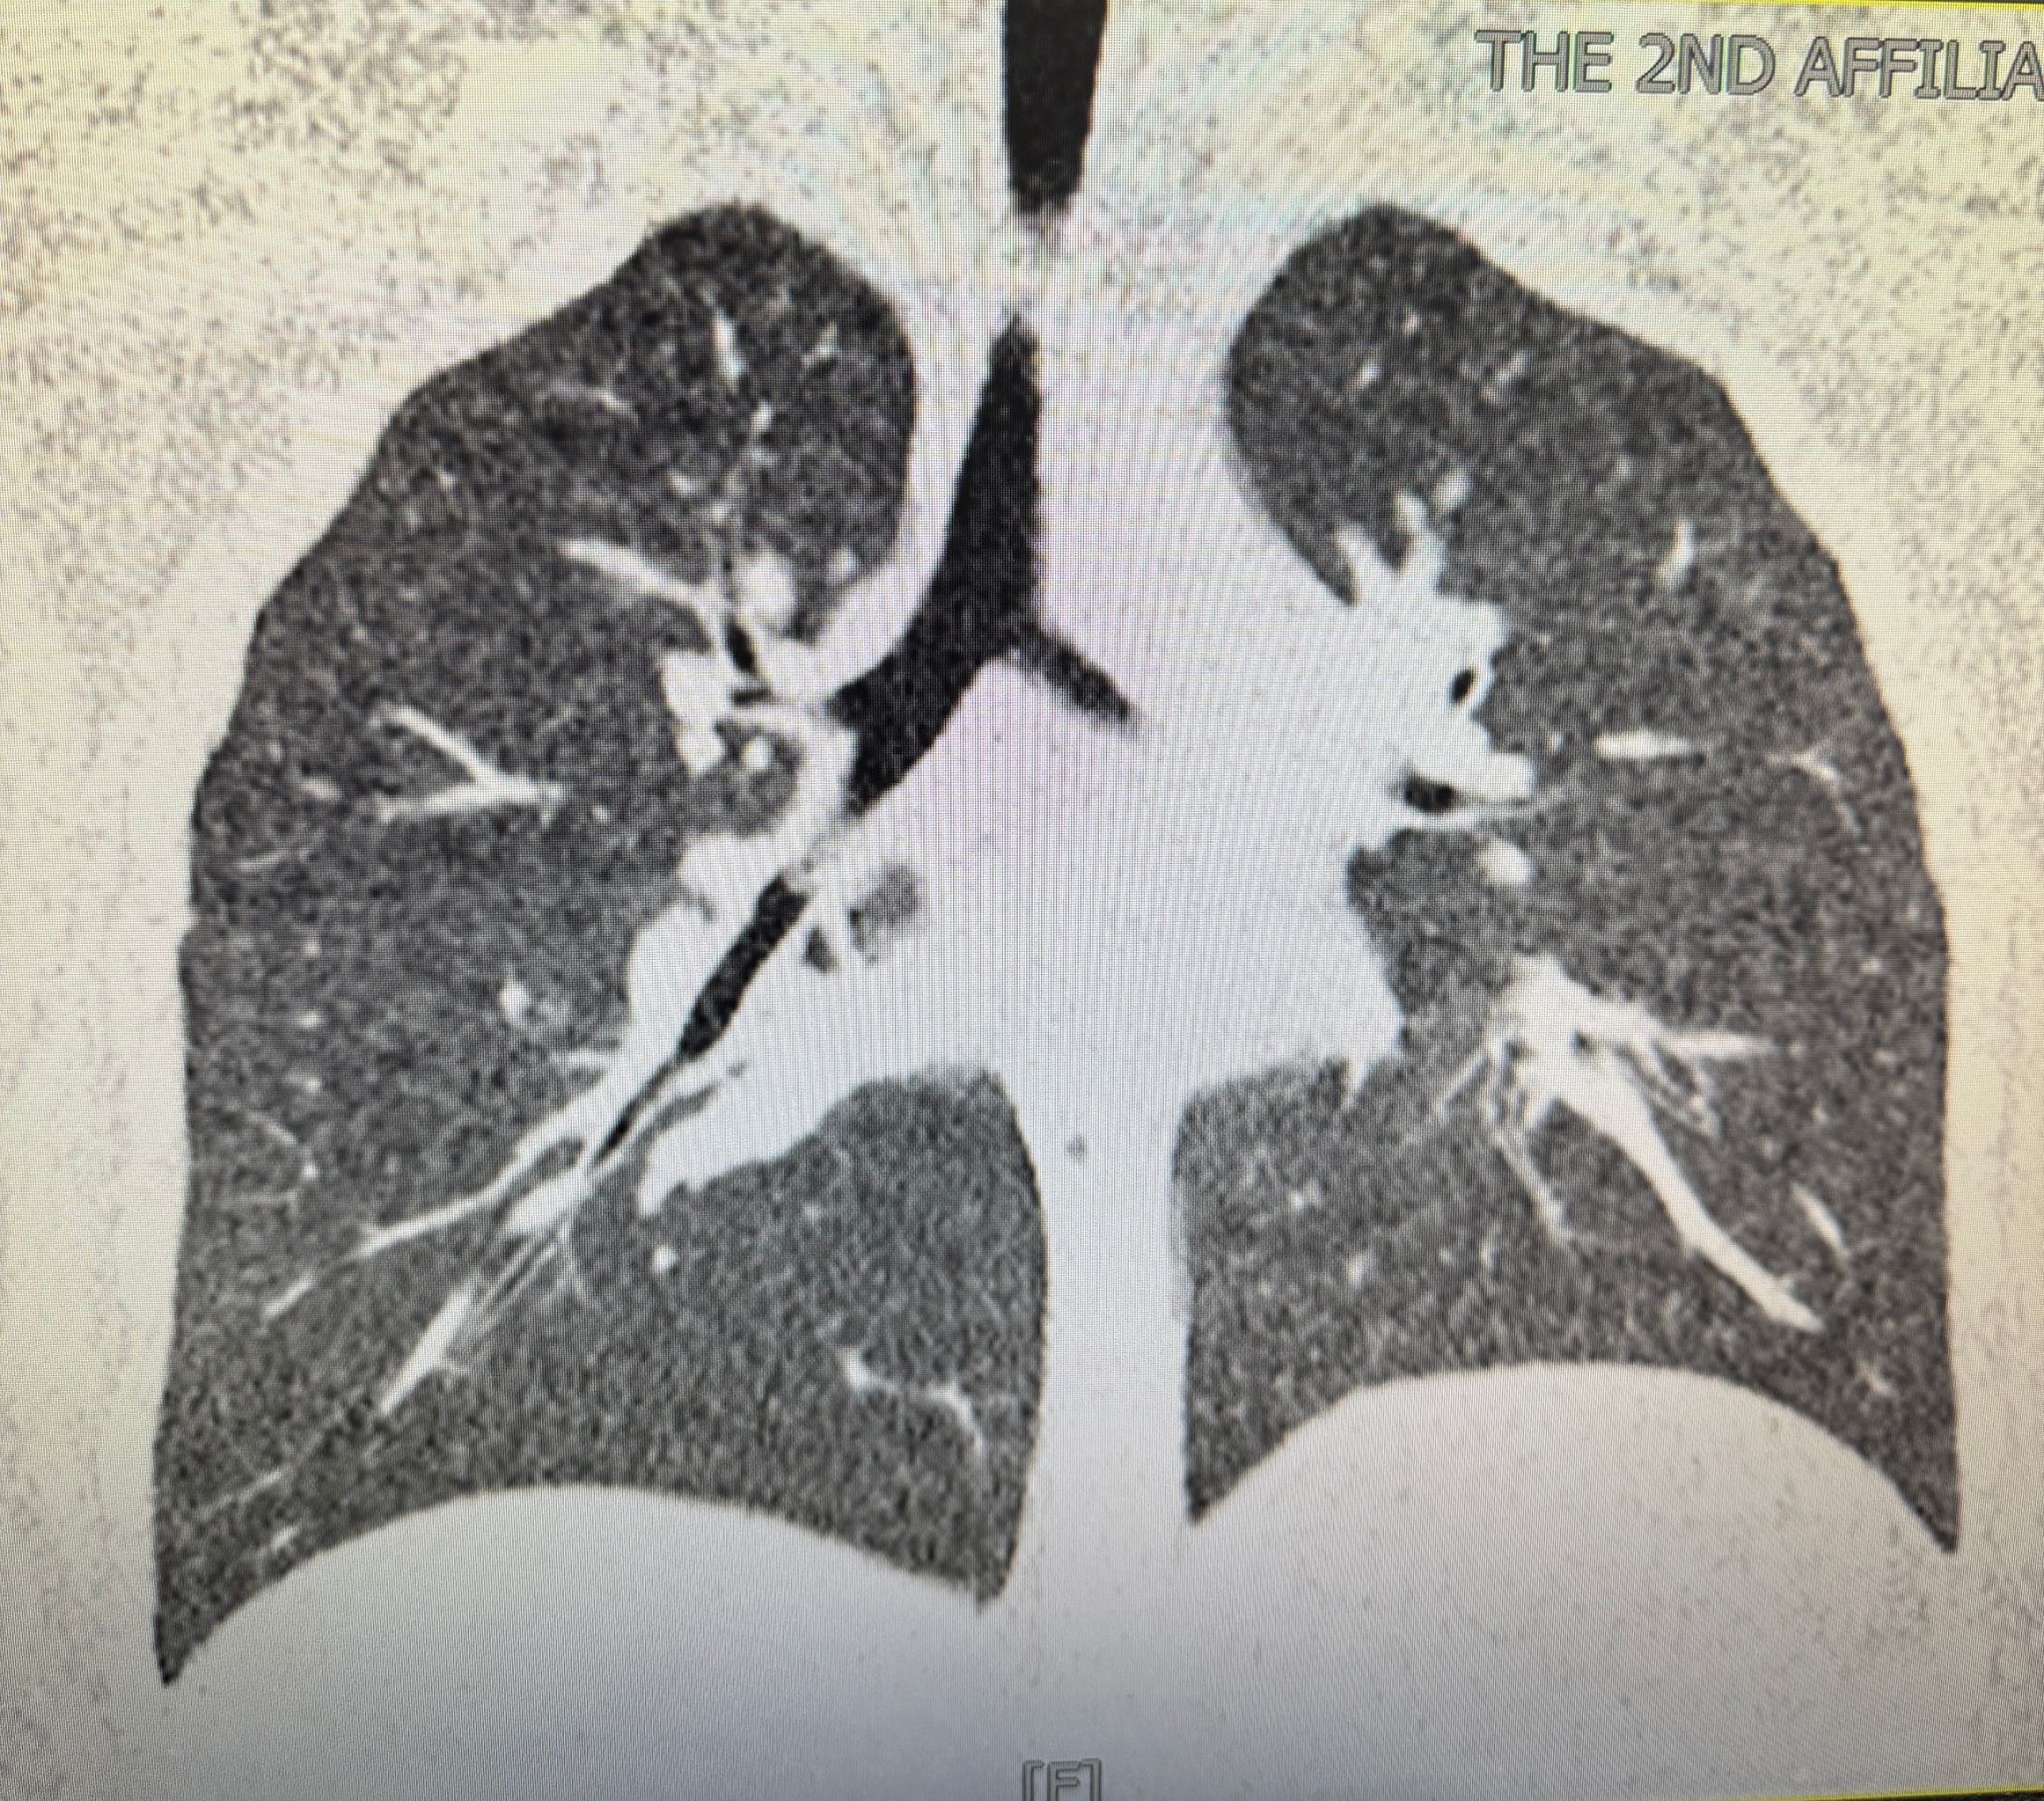

一场与时间赛跑的生命救援就此展开。值班医生张璐瑶、折宁宁立即查看患儿,兰兰呼吸急促,阵发性咳喘,听诊右肺中下叶呼吸音明显减弱,推测为右侧支气管异物。气管三维重建CT证实,一枚圆柱形异物嵌顿于右侧支气管中下叶开口处,伴右肺中叶、下叶肺不张。接到汇报后,耳鼻喉科胡娟副主任迅速组织急救,分析病情:呼吸道异物是我科常见急症,但该患儿吸入的笔帽外壁完全贴合支气管壁,内壁光滑短小,不利于钳夹,且一端完全封闭,造成气道机械性阻塞,支气管腔内负压形成,随呼吸运动负压逐渐加重,不利于笔帽松动向外拉出;因此,经气管镜钳夹异物向外取出的过程较为困难,可能造成张力性气胸或窒息,危及生命。胡娟副主任向家长介绍病情,请家长提供与吸入异物相同的笔帽,以筛选合适器械,模拟手术过程。同时请麻醉科、小儿内科、小儿外科紧急会诊,耳鼻喉科值班团队实施心电监护及吸氧支持,紧急完善各项术前检查。根据家长提供的笔帽,多学科共同制定手术预案,准备不同型号气管镜、异物钳、取石网篮、Nd.Yag激光等,以备在笔帽封闭端或内壁打孔,方便异物钳夹持。